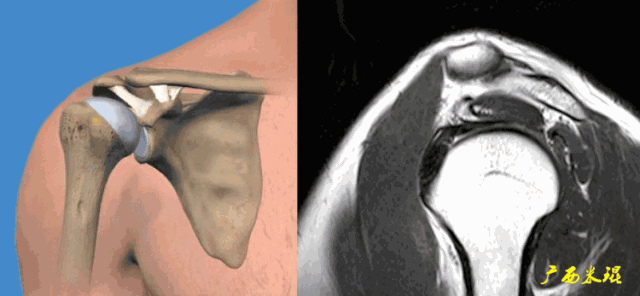

肩袖(Rotator cuff)损伤由Smith于1834年发现并命名,指组成肩袖的冈上肌、冈下肌、肩胛下肌和小圆肌的损伤。肩袖是以上4条肌腱共同组成的功能复合体,呈一个袖套状包绕肱骨头,维持盂肱关节的稳定,同时提供肩关节活动时所需的动力。

冈上肌和冈下肌在肱骨大结节上有共同止点,冈上肌和肩胛下肌在结节间沟处共同包绕肱二头肌长头腱。这样紧密的关系预示着肩袖的某一部分组织发生病变一般都会波及其余的肩袖组织,也是我们MRI阅片中必须要注意的。

正常肩袖的MRI表现

各个序列肩袖均表现为均匀的低信号,是肌腱的延续。